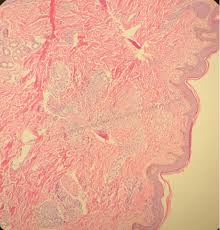

Sarcoidosis is a rare disease caused by inflammation. These lumps are called granulomas and can affect how the lungs work. Furthermore, lung cancer symptoms, such as a persistent cough, back pain or weight loss, can resemble a cold or bronchitis and may not raise suspicions of lung cancer, herrera adds. 53 patients were found to have cancer after their sarcoid diagnosis of whom 27 were male (51%) and 26 were female (49%). There are currently no formal recommendations to guide the differential diagnosis workup between the evolution of lymphoma or a solid cancer and a granulomatous reaction associated with neoplasia.

Apparently, lymphomas can sometimes harbor sarcoidal granulomas within cancer — and this change, although rare, is thought to perhaps reflect an immune reaction to the cancer tumor, and not the systemic disease, sarcoidosis. These lumps are called granulomas and can affect how the lungs work. If it is sarcoid, then you can get the help you need for this condition. Sarcoidosis can also affect calcium metabolism, the nervous system, the liver and spleen, muscles, bones and joints, the kidneys, lymph nodes, or any other organ. This can lead to misdiagnosis as conditions such as irritable bowel syndrome (ibs). What every physician needs to know. From my experience being diagnosed with lung cancer which fortunately turned out to be sarcoidosis of the lungs , then four years later suspected lymphoma when i had swollen lymph nodes in my neck. When sarcoidosis affects the lungs, symptoms can mimic idiopathic pulmonary fibrosis including shortness of breath and a dry cough. Only 10 similar cases had been reported previously. 53 patients were found to have cancer after their sarcoid diagnosis of whom 27 were male (51%) and 26 were female (49%). Despite careful preparation, it thus remains difficult to distinguish between these conditions even when lymph nodes are strictly evaluated. Sarcoidosis patients may be misdiagnosed with tuberculosis, lymphoma, or lung cancer 4 . Although it is most commonly thought to be a lung disease, sarcoidosis has been shown to affect almost any organ.

That same fungal infection is often frequently mistaken for squamous cell carcinoma, or skin cancer, when it shows up on the skin. Sarcoidosis is a rare disease caused by inflammation. It usually occurs in the lungs and lymph nodes, but it can occur in almost any organ. Only 10 similar cases had been reported previously. When sarcoidosis affects the lungs, symptoms can mimic idiopathic pulmonary fibrosis including shortness of breath and a dry cough. No prior imaging was available for comparison. After some conversations and research i now know sarcoidosis can be mistaken for cancer. A condition called sarcoidosis, most commonly found in the lungs, can be mistaken for cancer, tuberculosis, or other infections, as its symptoms are similar. That time between when they tell you the possibilities and when you get the results from the biopsy is terrifying. Occasionally this pattern of fibrocystic change is seen in the lower lung zones, an atypical location that may cause pulmonary sarcoidosis to be mistaken for. Which was a flare up of sarcoidosis. A permanent pathological slide, however, indicated that right interlobar (#11s) lymph nodes involved both sarcoidosis and lung cancer metastasis. Can sarcoidosis turn into cancer.